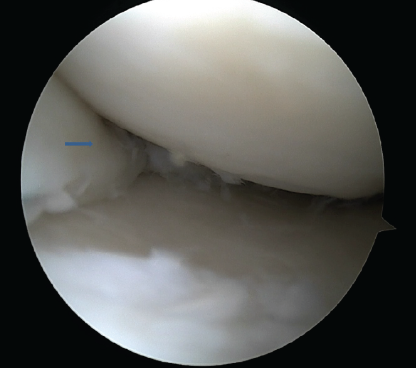

A simple and inexpensive technique was used for outside-in stitches. An 18-gauge spinal needle, which is pre-loaded with no.1 polydioxanone (PDS), is inserted into the joint cavity from outside to inside and passed through the upper surface of the meniscus. For a medial meniscus tear, the viewing portal is the anterolateral portal, and instrumentation is through the anteromedial portal. For a lateral meniscus tear, it is usually the opposite. However, the versatility of changing the portals or even an additional trans-patellar tendon portal is often necessary. Once the PDS is successfully inserted into the joint through the 18-gauge needle, it is retrieved through the anteromedial portal. A simple knot is made with the end of the PDS through which a No. 0 FiberWire is passed. The PDS from the side of the joint is pulled back. Along with the PDS, the FiberWire gets railroaded across to the side of the joint. The spinal needle was inserted again through the same skin puncture point, changing the direction subcutaneously to ensure the spinal needle passes between the lower surface of the meniscus and tibial plateau. The process is repeated, and both ends of FiberWire are retrieved to the medial side of the joint. A safety incision is made to retrieve both ends of the FiberWire. It is important to ensure that the soft tissue between the 2 ends of FiberWire is cleared to allow the stitch to sit on the capsule. An Aberdeen sliding knot is made and reduced to adequate tightness to ensure that the meniscus tear is closely approximated, but at the same time, avoid over-tightening. Then, subsequent half-hitch knots are made. For the lateral meniscus, the outside-in stitches were applied just anterior to the popliteus muscle. Once both the menisci were well peripheralized, the floppy posterior parts of the menisci were addressed using all-inside stitches. The posterior horn of the lateral meniscus was repaired with three vertical mattress sutures using the all-inside 24° DePuy Mitek device (Truespan meniscal repair system) at an interval of 5–10 mm from each other. Most of the devices come with 18 mm as a pre-set depth on opening the package. In total, 18 mm will be sufficient for most tears except when placing the stitch in the central part of the meniscus. The medial meniscus exhibited a displaced bucket handle tear extending from the body to the posterior horn. Initially, the meniscus was reduced using a trocar. The anterior horn and the body were repaired employing an outside-in technique using an 18-gauge spinal needle and No. 2-0 FiberWire. The posterior horn was repaired with 2 all-inside sutures (12° DePuy Mitek). While repairing the medial meniscus, its paramount to hold the knee in 20–30° of flexion and valgus stress to be provided to open up the medial joint space (Figs. 4 and 5).

Figure 5: Completely reduced lateral meniscus tear with a combination of outside-in and all inside stitches (arrow indicating reduced lateral meniscus).